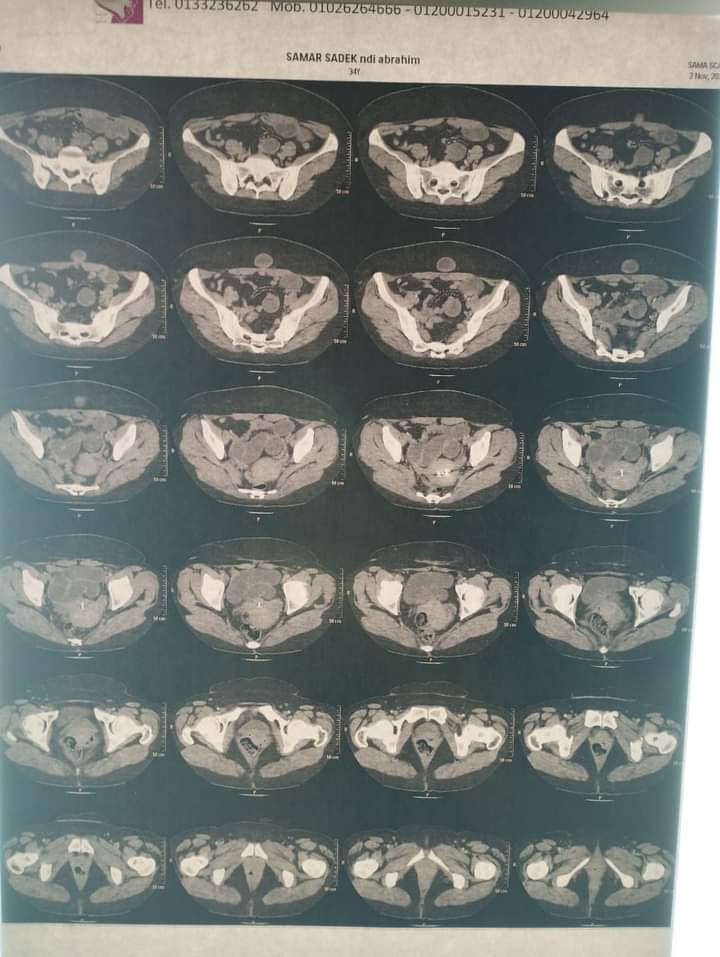

قام فريق الجراحة بمستشفى بنها التعليمى بإجراء استكشاف جراحي لحالة انسداد معوي منذ خمسة ايام  لمريضة ٣٥ سنة تعاني من جفاف شديد و انقطاع البول و هبوط في الدورة الدموية

حيث تم إجراء الفحوصات للمريضة والتى أثبتت وجود فتاق مختنق في جدار البطن من نوع نادر سبجيلي (speglian hernia).

و تم تحضير الحالة بالعناية الجراحية و إجراء جراحة عاجلة الساعة الواحدة صباحا و الحالة الان مستقرة بالعناية الجراحية بالمستشفي.